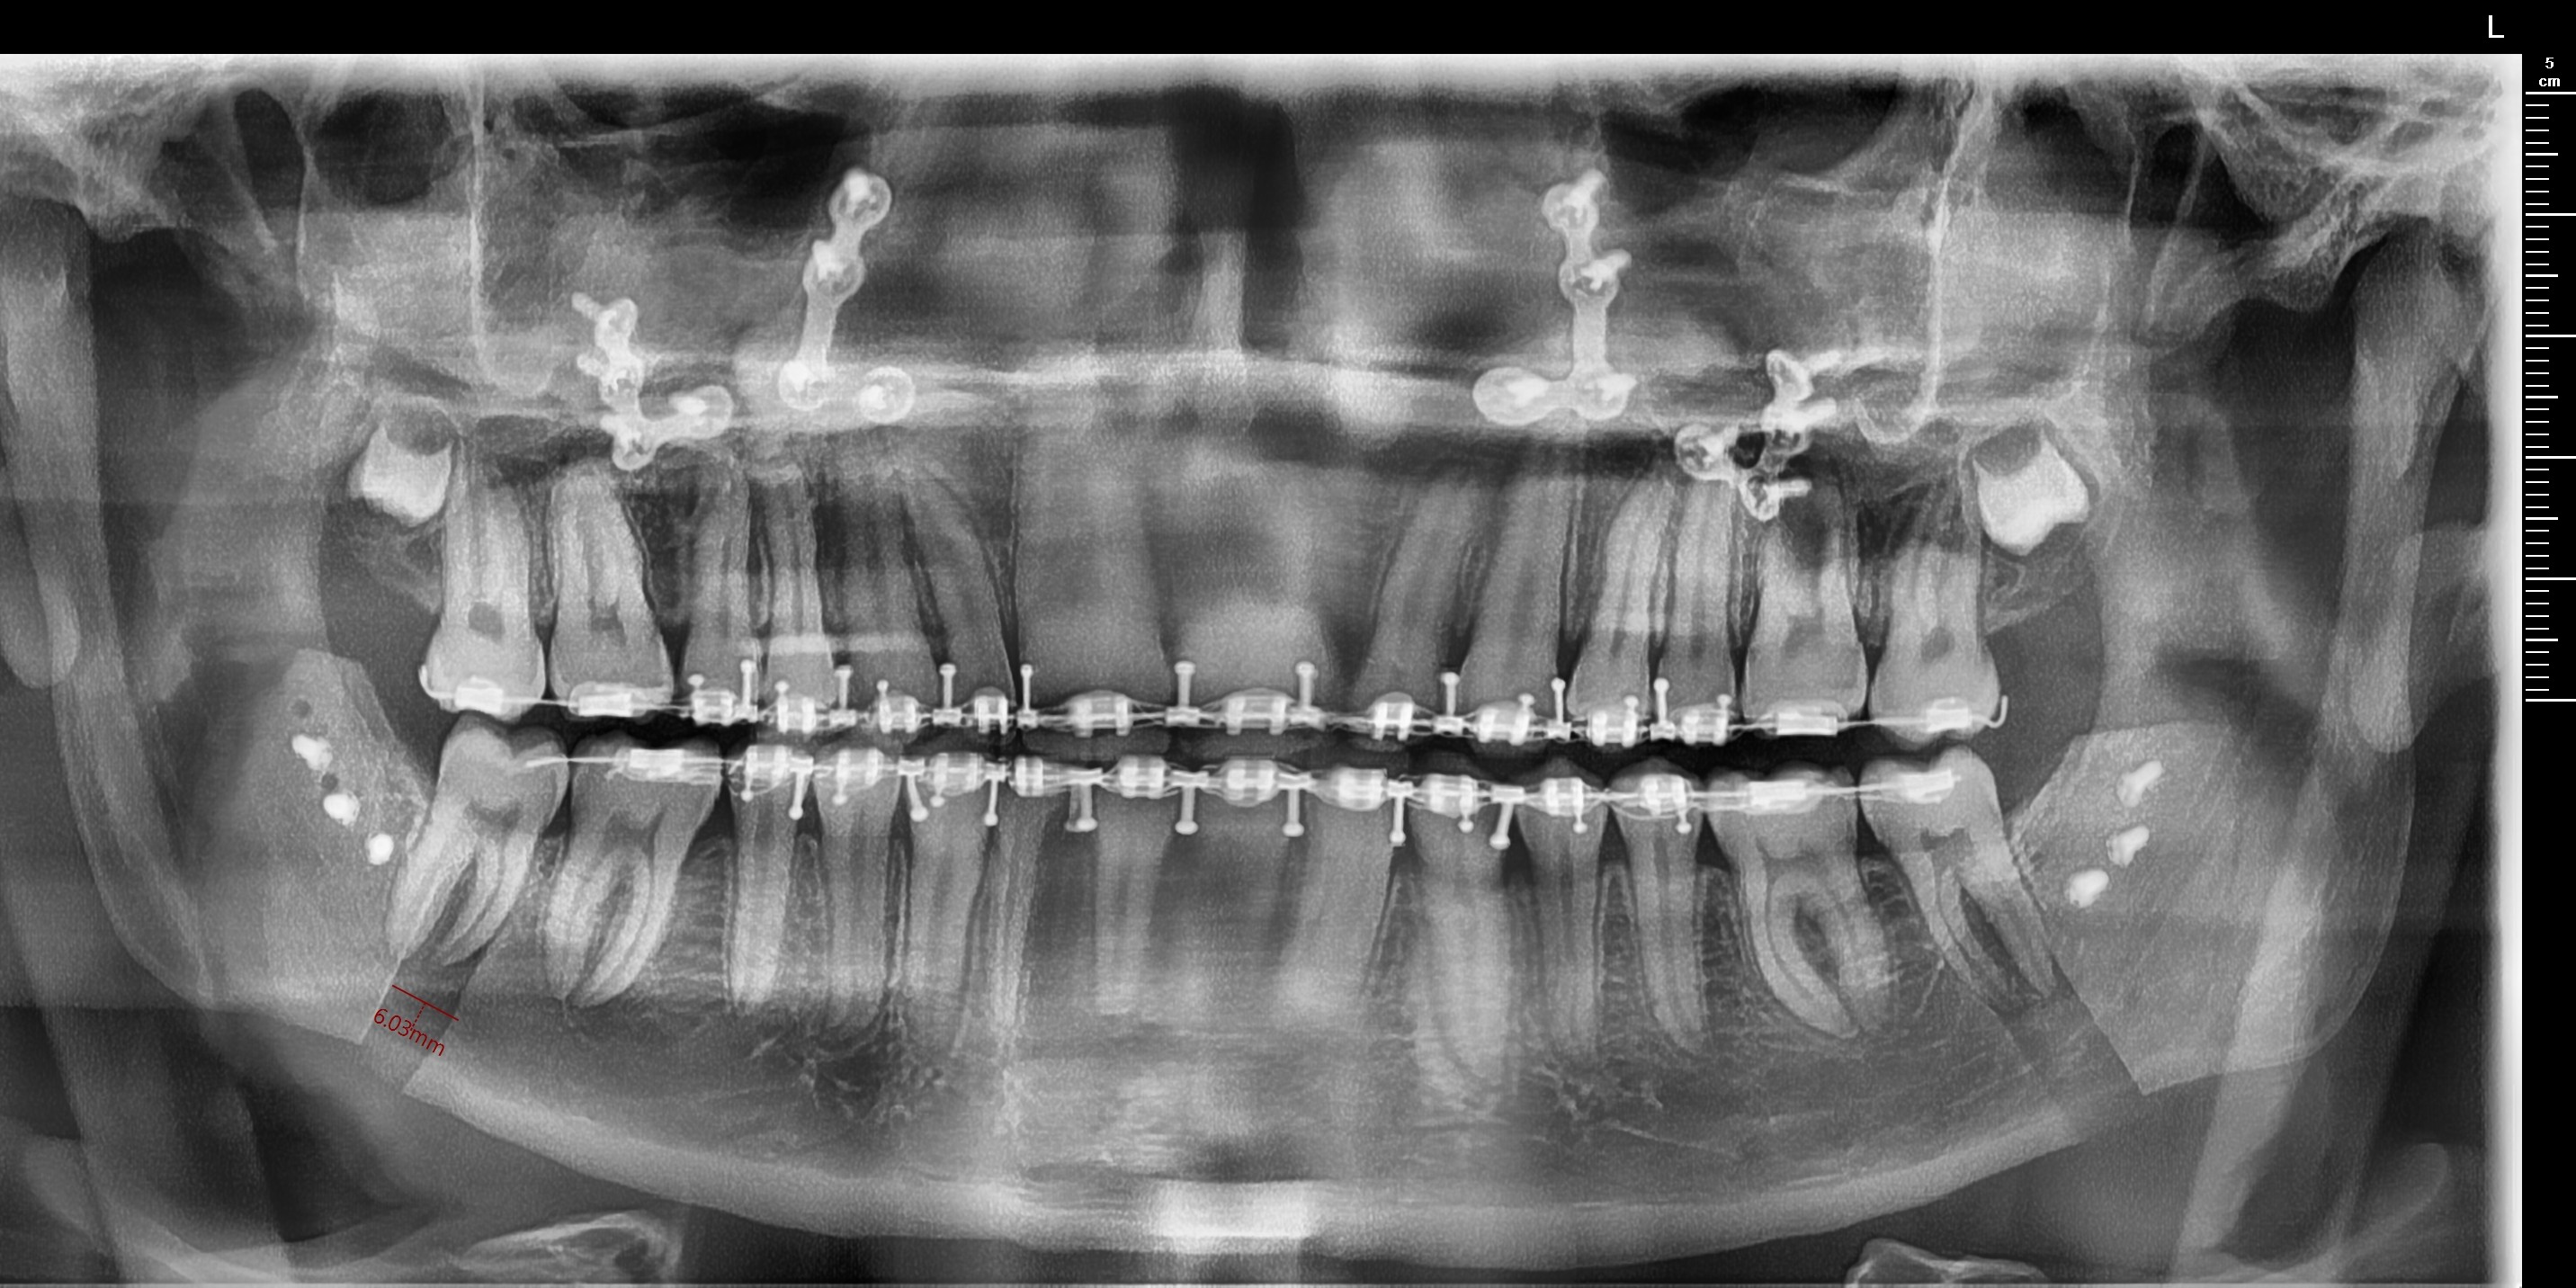

Got a Bimax late september via insurance. These were the movements planned.

LEFORT 1: 2MM ADVANCEMENT

BSSO: 8MM ADVANCEMENT

2° CCW ROTATION

Although post-bimax marpe is rare, I believe I still qualify. my smile is narrow asf and struggle to put my tongue on my the top of my mouth. Finding an orthodontist in the Netherlands willing to provide this is gonna be hard but there are some promising orthodontists im planning to consult. One of these is Aldin Kapetanovic. He has published multiple research papers about marpe and even created his own design: Dutch Maxillary Expansion Device. It contains 4 miniscrews and is 3d printed (picture below). Can those knowledgeable on MARPE DESIGN advise if this is a good design? Would really help me out as i'm not too knowledgeable.